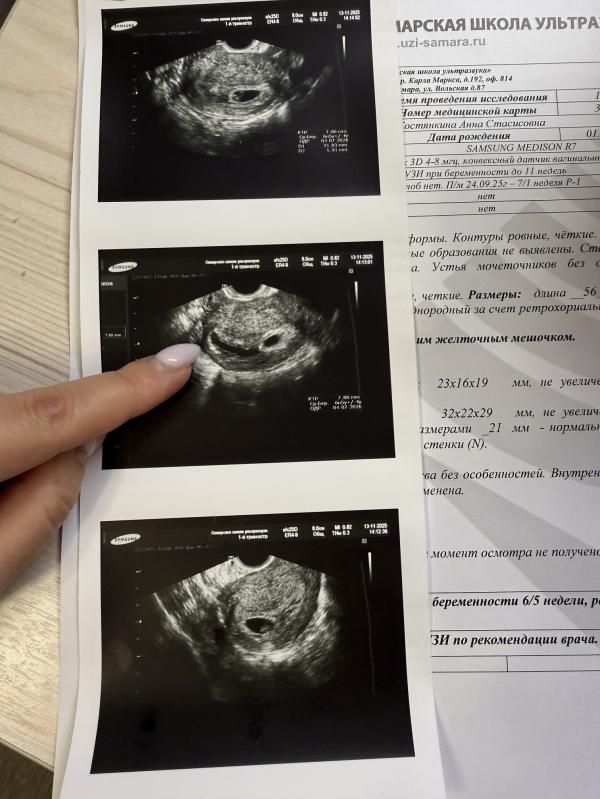

Девочки,была на узи,сердечко бьется,плод развивается,НО в матке гематома 32/6мм достаточно большая,что делали,если у кого-то было? Боюсь очень😞